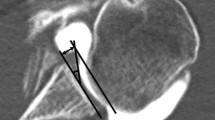

The assessment of the osteophyte was performed in T1-weighted MRI sequences in the coronal plane with the biceps anchor in the most prominent position (Fig. 1, P1, P4). A circle was placed into the humeral head with a tangent at the 12 o’clock position and at the 3 o’clock and 9 o’clock positions for the right and left shoulders, respectively (Fig. 1, P2, P5). The size of the osteophyte was measured from the tangent of the circle perpendicular to the highest point of the osteophyte (Fig. 1, P3, P6). Occurrence of inferior humeral and/or glenoid osteophyte was assessed using MRI. The grade of osteoarthritis was evaluated based on the Samilson–Prieto classification (Tables 3, 4). Labrum interior morphology was measured on the same T2-weighted sequence and graduated from 0° to III° according to descriptive graduation, as published by Randelli et al. (Table 7). Separated for the anterior and inferior portion, the labral height (LH) and glenoid height (GH) were measured as the maximum distance (in millimeters) to the lowest portion of the glenoid cavity (Table 8). The labrum glenoid height index (LGHI) was measured as the quotient of the labral height to the glenoid height for the anterior and inferior area. Analogue, the anterior and inferior labrum glenoid slopes (labrum glenoid slope = LGS) were defined as the angle between the tangent at the lowest point of the glenoid cavity and the tip of the maximum labral height (Table 8). These parameters were measured in transaxial PDW EXP-weighted images for the anterior capsulolabral complex and in coronal T2-weighted images for the inferior area. MRI assessments were performed according to the established protocol of Yoo et al. [34]. The labrum MRI assessments were performed according to the established and validated protocol of Yoo et al. [34], which was applied in several comparable protocols [31, 32].